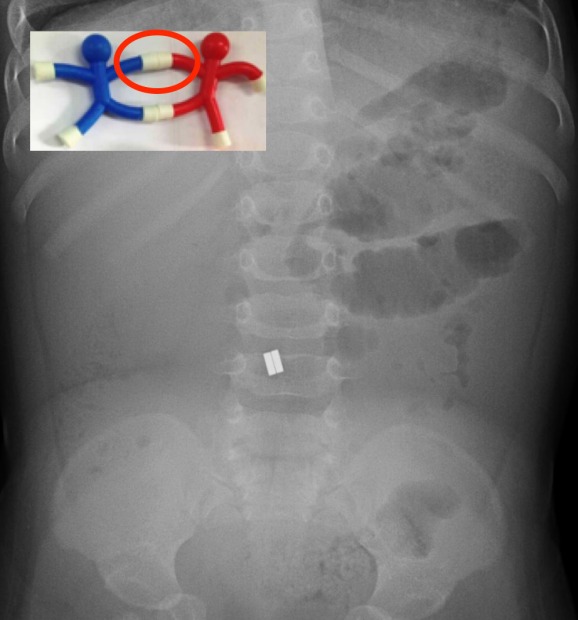

The two magnets inside the toddler’s stomach

The representative said the second child was brought in as a suspected case of head injury as he was crying and vomiting.

“The parents thought that something had fallen on him and they suspected a head injury as the child vomitted.

“A CT scan revealed it was not the case. But the child vomited in the emergency department and the doctor suggested a detailed investigation, following which two magnets were found inside his stomach.”

Sources told the GDN that the child had swallowed magnets behind fridge memos.